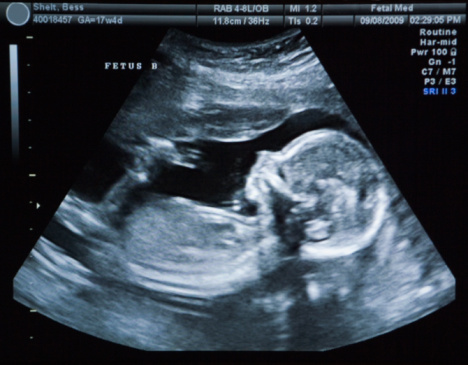

سونوگرافی:

سونوگرافی یک راه غیرمخرب برای تعیین جنسیت جنین است؛ استفاده از سونوگرافی برای تعیین جنسیت جنین فقط از هفتههای ۱۸ تا ۲۰ به بعد ممکن است.

تکنسین اولتراسوند ممکن است در هنگام اسکن نتواند جنسیت جنین را تشخیص دهد زیرا ممکن است جنین در موقعیت ایدهآل قرار نداشته باشد یا بارداری به اندازه کافی پیشرفت نکرده باشد.